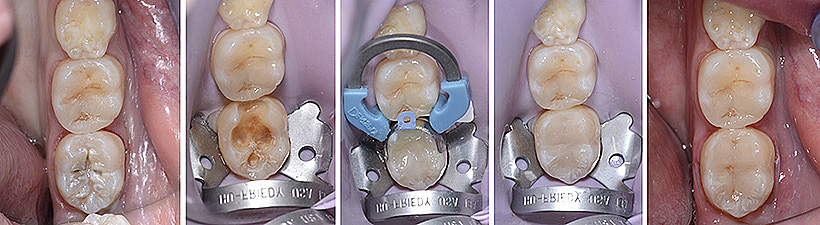

L'impiego della diga di gomma in questo tipo di riabilitazione è fondamentale, dal momento che i materiali estetici attualmente in uso sono estremamente sensibili all’umidità e richiedono un ambiente il più possibile isolato per garantire un restauro tecnicamente corretto e durevole nel tempo.

L’odontoiatria conservativa moderna è basata sul concetto di minima invasività, con la rimozione del solo tessuto cariato e la sua sostituzione con un materiale da restauro, che viene legato direttamente al tessuto sano. Negli ultimi anni sono state abbandonate le amalgame in metallo a favore dei compositi, materiali più resistenti e più estetici. Grazie alle caratteristiche adesive dei materiali compositi, viene rimosso il solo tessuto cariato, a differenza di quanto avveniva con l’utilizzo dell’amalgama d’argento, che richiedeva una preparazione del dente ritentiva e pertanto una cavità più ampia con la rimozione anche di tessuto dentale sano.

Prima dell’otturazione vera e propria si procede a ripulire la cavità dal tessuto cariato. I tessuti del dente, smalto e dentina, verranno successivamente mordenzati con un acido particolare per migliorare la successiva adesione del composito. Una volta posizionato nella cavità del dente il composito viene utilizzata una luce speciale per indurire e cementare il materiale al dente stesso. Infine il restauro in composito viene modellato e lucidato per ricreare un aspetto pari allo smalto del dente naturale.